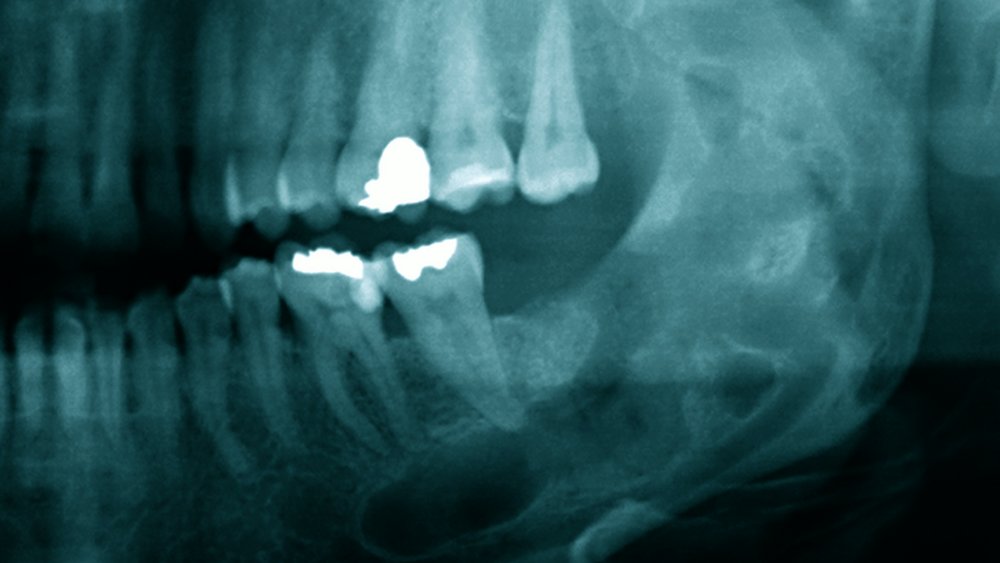

Eine 52-jährige Patientin stellte sich 2015 zur regulären Kontrolle nach der Entfernung einer Keratozyste im linken Unterkiefer im Bereich des distalen Corpus und aufsteigenden Unterkieferastes vor (Abbildung 1). Es hatte sich damals um eine unilokuläre Läsion gehandelt. Der Befund war über eine laterale Osteotomie im Sinne einer Zystektomie entfernt worden.

Bis 2017 hatten sich keine Auffälligkeiten gezeigt. Nun stellte sich in der Kontrolle mittels Panoramaschichtaufnahme radiologisch der Verdacht auf ein Rezidiv. Im Bereich des Corpus-Kieferwinkel-Übergangs zeigte sich eine blasig anmutende Transluzenz knapp oberhalb der Projektion des N. alveolaris inferior. Sensibilitätsausfälle lagen nicht vor. Die erweiterte Bildgebung mittels digitaler Volumentomografie bestätigte eine Lage direkt cranial des Nervens mit einem Durchmesser von 0,7 cm x 0,5 cm x 0,5 cm (Abbildung 2).